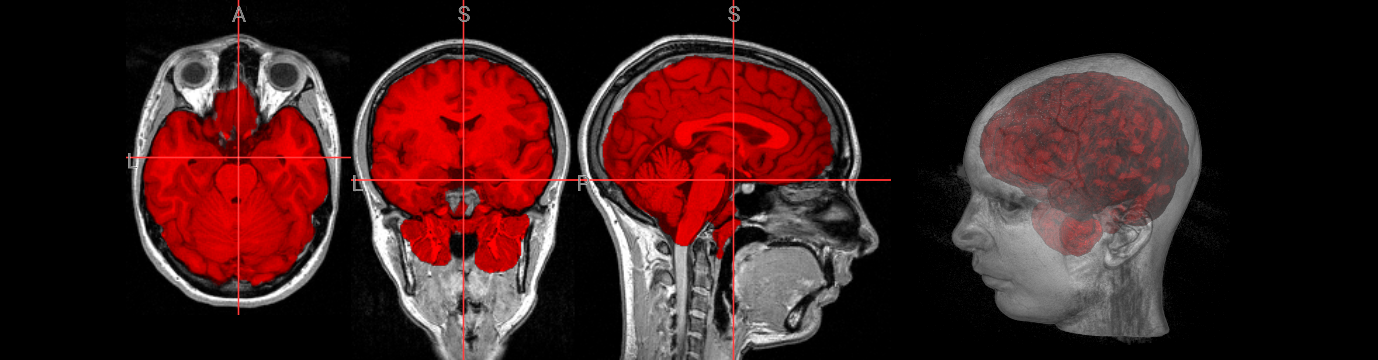

Brain extraction is a fundamental preprocessing step in neuroimaging analysis, particularly critical for structural image segmentation where precision matters most. While BET is straightforward to use, achieving optimal results often requires understanding how to fine-tune parameters for challenging datasets. This interactive version covers the core BET fundamentals, including parameter adjustment techniques for difficult images, and troubleshooting approaches for problematic cases. The hands-on format allows you to experiment with different settings and immediately see their effects on brain extraction quality.